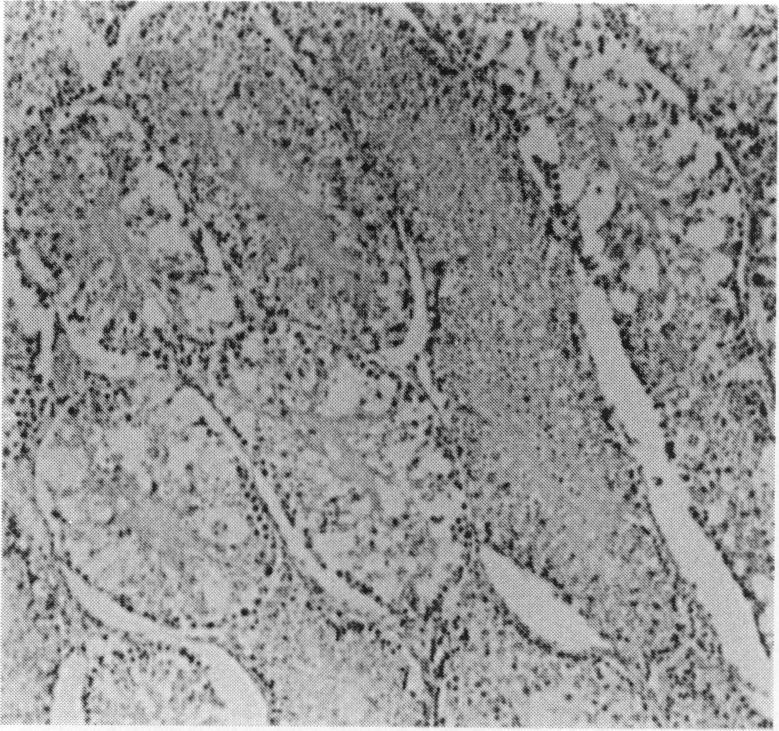

Testes of 8-week-old male Syrian hamsters which were inoculated intraperitoneally with 10(5) plaque-forming units of the D variant of encephalomyocarditis virus (EMC-D) were examined virologically and histologically. Viral replication was detected from 1 day post inoculation (1 DPI), became more prominent 3 DPI, and was no longer demonstrated 7 DPI. The weight of testis decreased in course of time and it was about 2% of that of control 6 weeks post inoculation (6 WPI). Histopathologically, degeneration and/or necrosis of germinal cells and spermatogonia were observed in many seminiferous tubules of all hamsters 3 DPI. At 7 DPI, luminal obstruction by cellular debris and subsequent replacement of them by mesenchymal cells were common in mildly atrophic tubules surrounded with inflammatory cells. Thereafter, atrophy of seminiferous tubules became severer with the lapse of time and, in addition to plasma cell infiltration, apparent increase in the number of Leydig cells was found in the interstices. No regenerative signs of germinal epithelia were detected by 6 WPI. This is the first report of EMC virus-induced orchitis.

对8周龄雄性叙利亚仓鼠的睾丸进行了病毒学和组织学检查,这些仓鼠经腹腔接种了10⁵ 个脑心肌炎病毒D变种(EMC-D)的蚀斑形成单位。接种后1天(1 DPI)检测到病毒复制,3 DPI时更为显著,7 DPI时不再检测到。随着时间推移,睾丸重量下降,接种后6周(6 WPI)时约为对照组的2%。组织病理学上,3 DPI时,所有仓鼠的许多生精小管中均观察到生殖细胞和精原细胞的变性和/或坏死。7 DPI时,轻度萎缩的小管内常见细胞碎片造成的管腔阻塞,随后这些碎片被间充质细胞取代,周围有炎症细胞。此后,随着时间推移,生精小管萎缩变得更加严重,除浆细胞浸润外,间质中Leydig细胞数量明显增加。6 WPI时未检测到生精上皮的再生迹象。这是关于EMC病毒诱导睾丸炎的首次报告。